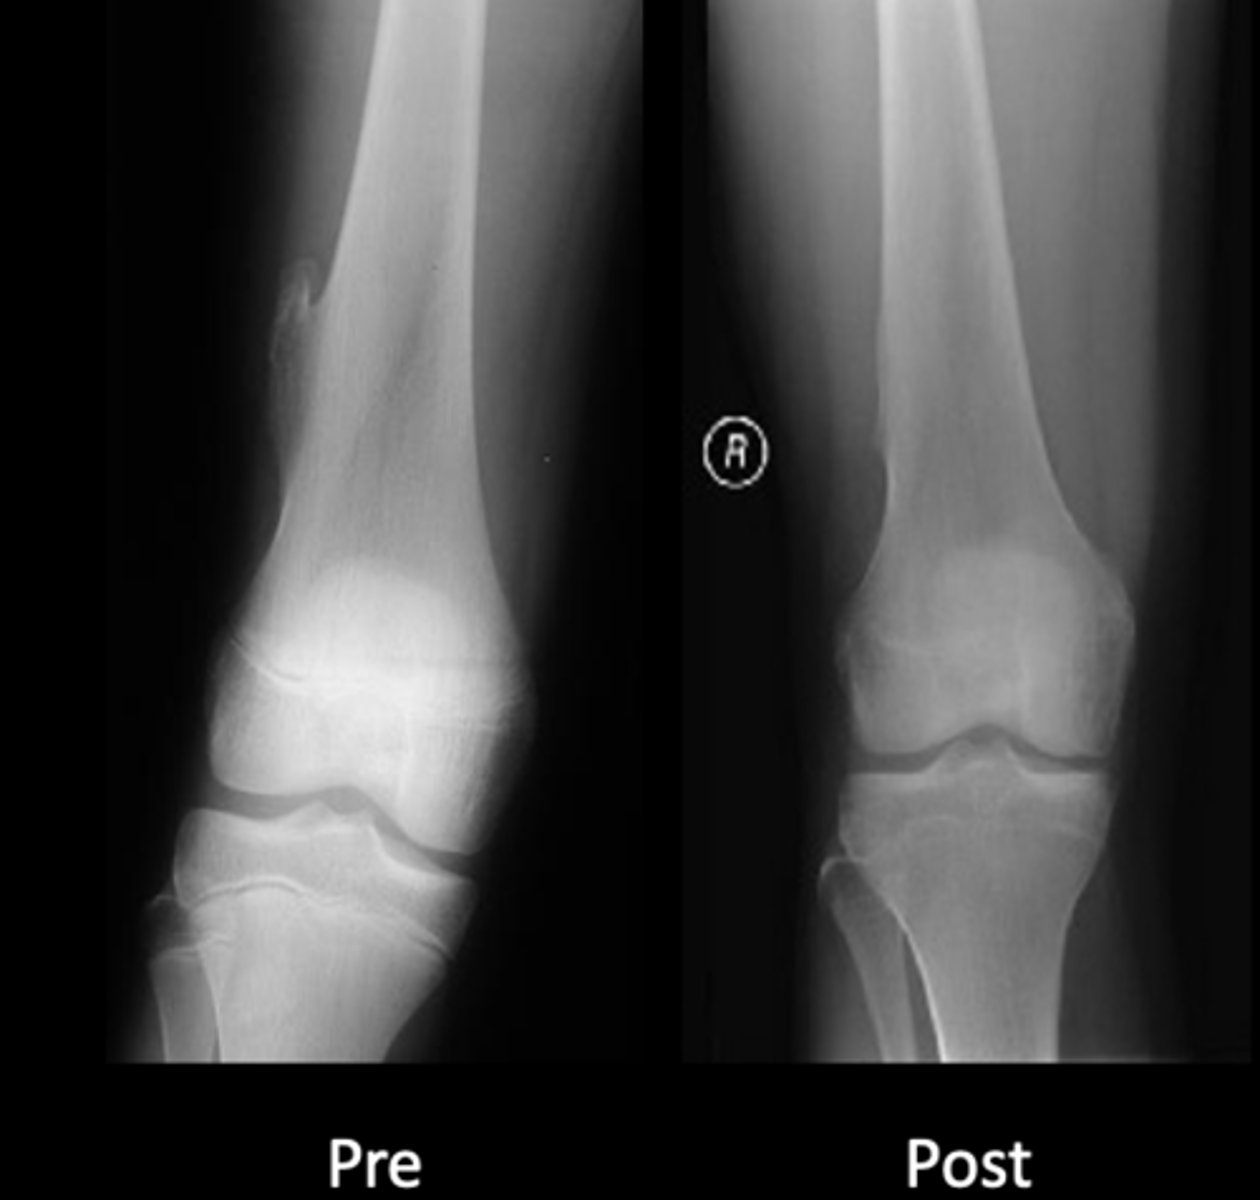

- Osteolytic

- Geographic

- Multiloculated and septated

- Begin in metaphysis

- Extend to subarticular bone

- Expansion

- Eccentric

- Quasi-malignant (can't tell benign from malignant)

State the imaging features of giant cell tumor

<p>State the imaging features of giant cell tumor</p>